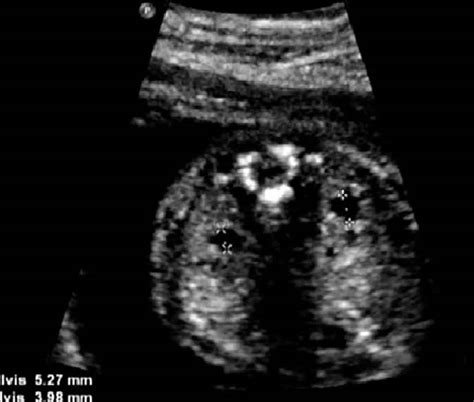

• Multicystic dysplastic kidney: This is a congenital condition where the kidney is composed of multiple cysts rather than functional tissue.

Pyelectasis of the fetus is typically diagnosed during routine prenatal ultrasound examinations. The diagnosis is based on the measurement of the anteroposterior diameter (APD) of the renal pelvis. The severity of pyelectasis is categorized as follows:

In addition to ultrasound, other diagnostic tests may be recommended, such as:

• Fetal MRI: This can provide more detailed images of the fetal kidneys and urinary tract.